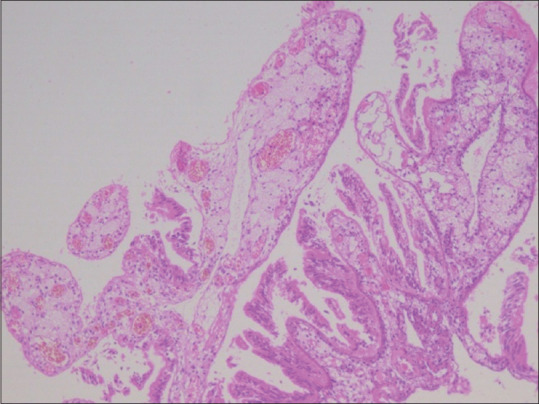

Uncommon presentations of granulomatous salpingitis are pseudoxanthoma salpingitis (PSX) and xanthogranulomatous salpingitis (XGS). The clinical features and image modalities can mimic ovarian malignancy. Thus, a proper pre-operative evaluation of this entity is vital to avoid radical treatment. Here, we report a case of a 31-year-old woman with primary infertility diagnosed with pseudoxanthoma salpinx. This patient was a known case of endometriosis and presented with gross ascites.

Abstract Image